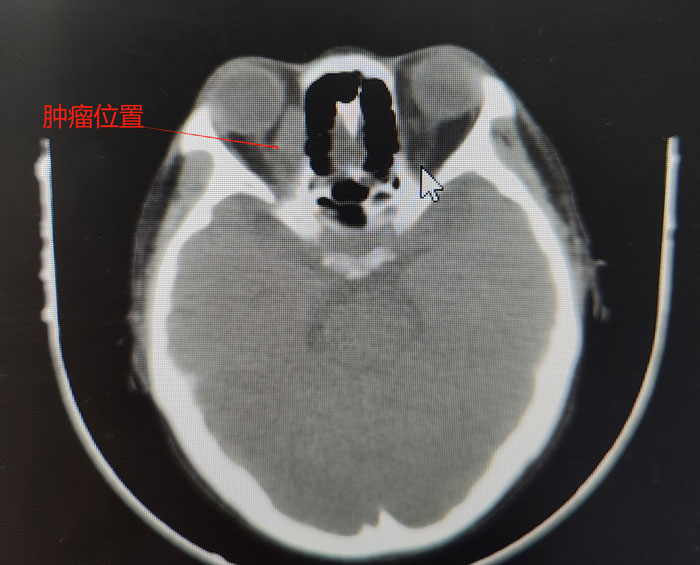

患者的病情非常特殊,其眼眶腫物內下方距離眶緣1cm處有一根較大的動脈血管,而腫瘤內側又緊挨著眼球,一旦穿刺出血,在患者血小板及白細胞危急值的狀態下開眶止血,無疑是難上加難。其次,術后暴發感染的風險也難以控制。同時,穿刺是為了更好地明確病理,需要選用粗針,這又極大增加了穿刺風險……面對如此復雜的形勢,在眼科腫瘤團隊和紀曉惠主任醫師的配合下,確定穿刺位置和進針方向、深度,經過三次“驚心動魄”的穿刺,順利取出三條魚肉狀腫物組織,病理診斷后,疾病的“真容”終于露出水面,患者確診為非霍奇金彌漫大B淋巴瘤。噬血細胞綜合征考慮為淋巴瘤繼發,需要積極控制淋巴瘤原發病。之后,患者前往我院血液中心接受進一步規范化精準治療。